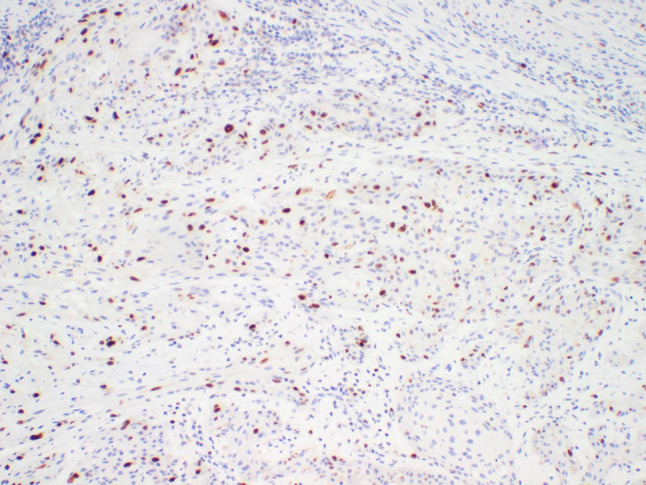

鳞状牙本质瘤(SOT)是一种极为罕见的良性上皮性牙本质肿瘤,呈鳞状分化。它是由纤维基质中大小不一、形状各异的细胞学平滑的成熟鳞状上皮细胞岛组成。在本报告中,我们介绍了一例罕见的上颌骨鳞状牙本质瘤(SOT)转变为分化良好的鳞状细胞癌(SCC)并累及翼管板的病例。据我们所知,文献中仅报道过两例SOT恶性转化的病例。在此,我们试图报告这一极为罕见的病例,以提高口腔颌面外科医生和病理学家对这一不寻常但严重的病例的认识,并对鳞状牙源性肿瘤进行文献综述。

Squamous odontogenic tumor (SOT) is an exceedingly rare, benign epithelial odontogenic tumor showing squamous differentiation. It is composed of variably sized and shaped islands of cytologically bland, mature squamous epithelium within a fibrous stroma. In this report, we present a rare transformation of a squamous odontogenic tumor (SOT) of the maxilla into a well-differentiated squamous cell carcinoma (SCC) with involvement of the pterygoid plates. To the best of our knowledge, only two cases of malignant transformation of SOT has been reported in the literature. Herein, we seek to report this extremely rare occurrence to raise awareness of oral and maxillofacial surgeons and pathologists of this unusual, but serious event and perform a literature review of squamous odontogenic tumors.